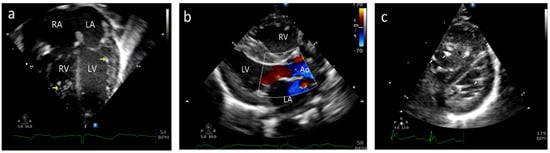

A 35-year-old gravida 2, para 1 mother was referred to our fetal cardiology center at 21 weeks of gestation for evaluation of fetal hydrops and bradycardia. An echocardiogram showed a ventricular rate of 74 bpm and an atrial rate of 144 bpm (Figure 1a). There was patchy hyperechogenicity of the atrial and ventricular walls, including the septum and chordae (Figure 1b/Video S1). The fetus had moderate tricuspid regurgitation (TR) and mild mitral regurgitation (MR), along with pleural and pericardial effusion, and a cardiovascular profile score of 8 (Figure 1c/Video S2).

Figure 1.

Case A: (a) M-mode echocardiogram showing atrioventricular dissociation; ‘a’ shows atrial contractions and ‘V’ shows ventricular contractions. (b) Antenatal echocardiogram, four-chamber view, showing hyperechoic papillary muscles (white arrow) in the left ventricle (LV) and right ventricle (RV). RA—right atrium, LA—left atrium. (c) Antenatal echocardiogram, four-chamber view, showing mild tricuspid regurgitation (white arrow) and no mitral regurgitation with normal atrioventricular valves.